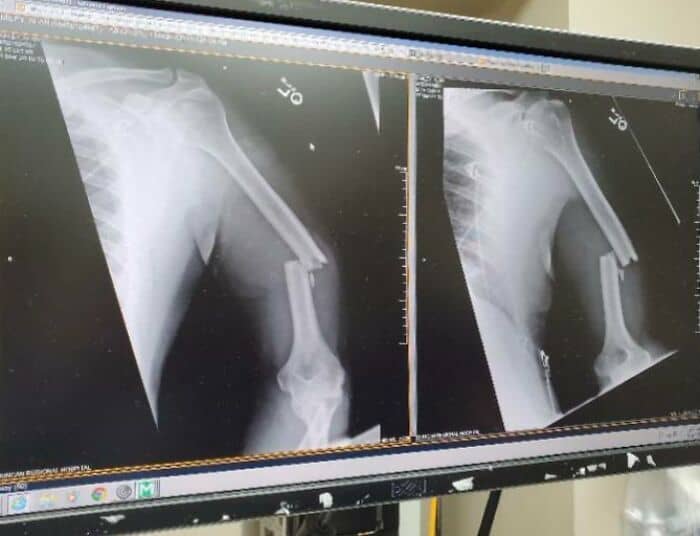

#26 My (Nearly 60 Y/O) Fathers Arm After Being Thwomped By A Cow This Morning